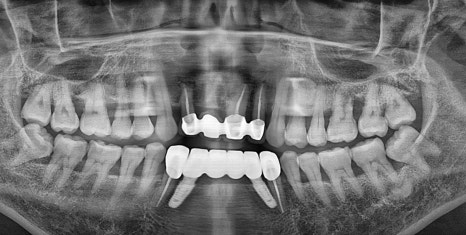

▲ 초진 파노라마

# 42 41 #31 32 치아는 흔들림이 심해 발치 후 임플란트 치료와 #42 41 치아쪽에는

뼈이식도 함께 진행 하였습니다.

#43 33 치아는 신경치료 이후 크라운치료로 마무리 하였습니다.

앞니는 치료도 중요하지만 심미적으로도 중요하기에 위 사진처럼

앞전에 말씀드린 '쉐이드 가이드' (치아 색상 측정기) 를 이용하여 주변의 치아 색상을 맞춰보고

▲ PMMA 착용 사진

위의 사진과 같이 중간에 PMMA이라는 임시 치아를 끼고 사용해보며

주변의 치아의 모양에 맞게 모양과 형태를 조절해본 후 최종 보철을 장착 하게 됩니다.